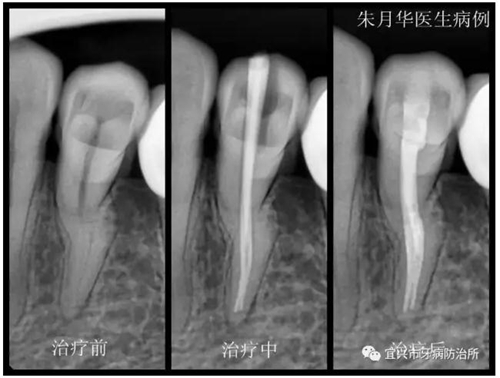

患者女,46歲,左下后牙疼痛不適數(shù)日余。經(jīng)檢查X線檢查,34根尖周牙周膜增寬,低密度影像,診斷為急性根尖周炎。處理:34局麻下開髓揭頂,測量根管長度,10號C+銼預彎在EDTA潤滑下疏通根管,疏通至20號K銼,隨后機用鎳鈦銼根管預備,疏通及根管預備期間次氯酸鈉不斷沖洗。封氫氧化鈣,ZOE暫封。一周后復診。去凈暫封物及根管內(nèi)封藥,隔濕,紙尖干燥,大錐度牙膠尖充填,隔濕,3M自酸蝕粘接劑+3M Z350光固化樹脂充填,調(diào)合,拋光。囑忌咬硬物,不適隨診。